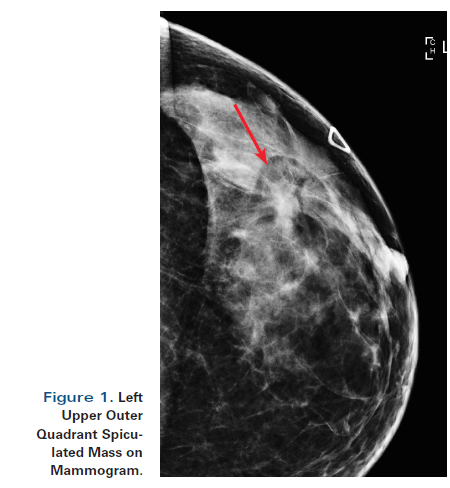

The right breast was normal to palpation Mammography revealed a solid, smooth nodule in the upper internal quadrant of the left breast (Fig 1) Ultrasound demonstrated an oval mass in the 10o'clock position of the left breast measuring 15×10 mm (Fig 2)Breast Cancer ICD10 Code Reference Sheet FEMALE Right C Malignant neoplasm of nipple and areola, right female breast C Malignant neoplasm of central portion, right female breast C Malignant neoplasm of upperinner quadrant, right female breast In the left breast there are two adjacent oval solid lesions measuring 5 and 65mm in diameter present in the 2 o'clock position In the 7 o'clock position there is a larger oval lesion measuring 10 x 5mm The appearance of each of the three lesions within the left breast is consistent, but not diagnostic of fibroadenoma